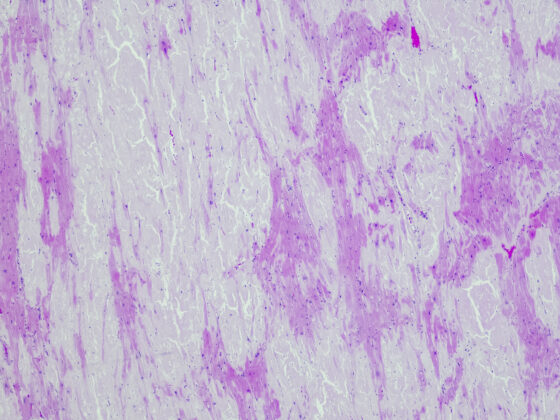

Wie Herkunft und Wohnort den CF-assoziierten Diabetes fördern